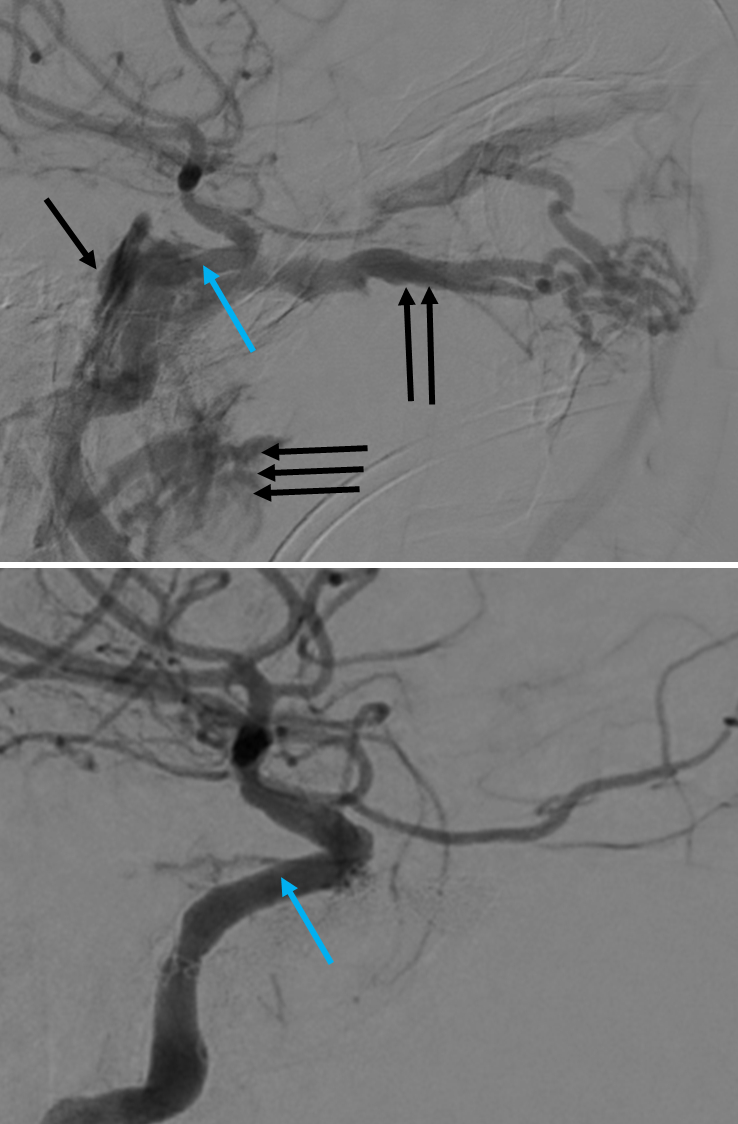

Cerebral angiogram, left ICA, AP projection pre (left) and post (right) transarterial balloon-assisted coil embolization. The patient presented with pulsatile tinnitus and left abducens nerve palsy six weeks after trauma. Angiography shows the Type A CCF with reflux inferiorly and contralaterally involving bilateral cavernous sinuses (black arrows). There is also evidence of steal phenomenon with decreased flow into the middle cerebral artery (red) territory and no visualization of the anterior cerebral artery territory. Post-embolization angiography shows the coil mass and obliteration of the CCF with restoration of normal arterial flow distally. Image courtesy of John D. Nerva, MD.

| current | 13:21, March 27, 2020 | 738 × 1,124 (244 KB) | Jacquelyn.Laplant (talk | contribs) | Cerebral angiogram, left ICA, AP projection pre (left) and post (right) transarterial balloon-assisted coil embolization. The patient presented with pulsatile tinnitus and left abducens nerve palsy six weeks after trauma. Angiography shows the Type A C... |